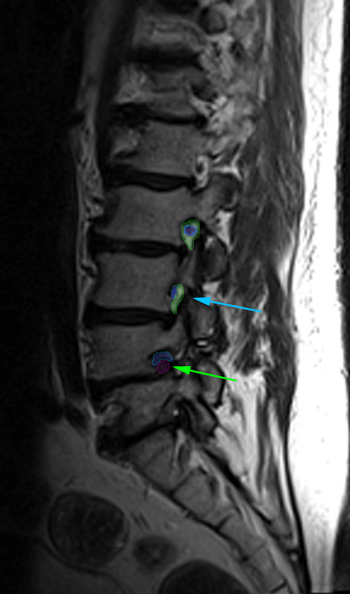

Αριστερά: Στένωση οσφυϊκού σπονδυλικού σωλήνα. Δεξιά:Φυσιολογικό νευρικό τρήμα στην κορυφή (πράσινο) με ελεύθερο νεύρο στο κέντρο (μπλέ περίγραμμα). Στενό τρήμα (κυανό βέλος) και ουσιαστικά κλειστό τρήμα,το οποίο εμπεριέχει μόνο το πιεσμένο νεύρο (πράσινο βέλος). Τεμάχιο δισκοκήλης εντός του τρήματος (κόκκινο περίγραμμα).